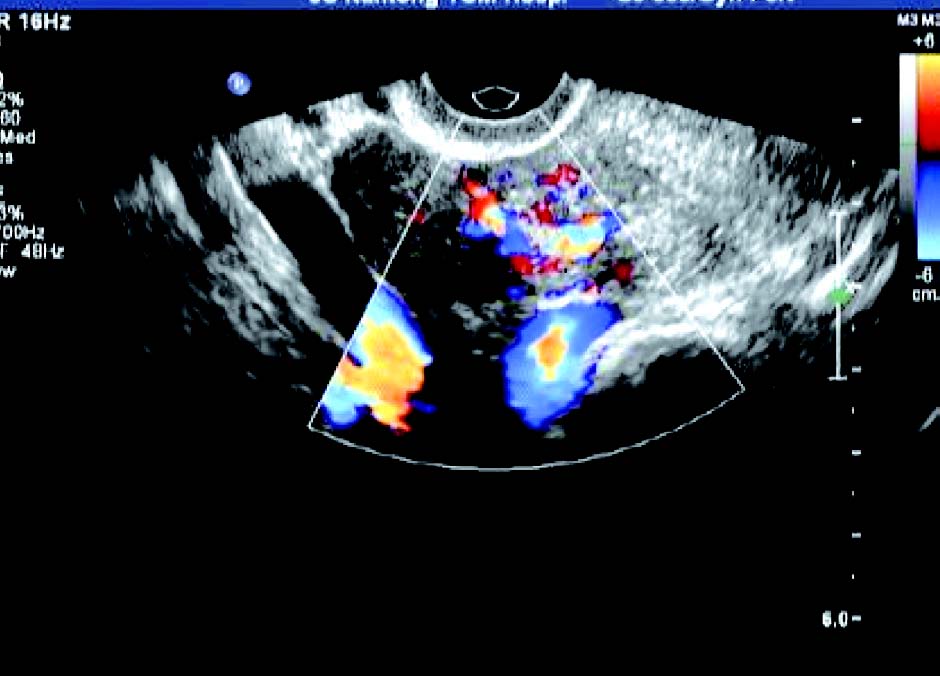

子宫增大,形态失常,浆膜向外呈圆形或半圆形突出,呈弱或中等回声,局部加压扫查,动态观察,瘤体与子宫无分离现象。CDFI 检测: 瘤周呈现环状血流信号,并向瘤体延伸。浆膜下肌瘤突入子宫两侧阔韧带称为阔韧带肌瘤,常显示为子宫一侧实质性圆形肿物,体积较大,仅一蒂状与子宫相连,易变性;蒂部彩色血流信号来源于子宫,其彩色血流信号环绕瘤体。

2. 肌壁间肌瘤

多呈低回声,大小不一,包膜完整,瘤体与宫壁正常肌层间界限清晰,周围显示环状彩色血流信号。肌瘤较大时,可压迫和推挤宫腔,使宫腔内膜回声移位或变形。